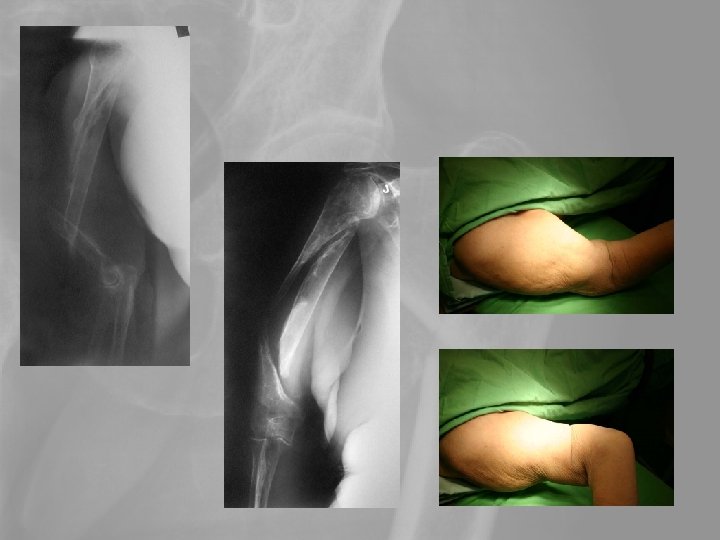

6. A proximalis humerusvég törései Idős betegek vállficam helyett a szenvedik el. A törés több darabos, porotikus. A konzervatív kezelés késői functionalis eredménye nem rosszabb, mint a műtétes kezeléseké. A vállprothesis eredményei messze elmaradnak a csípőízületi prothesisek késői funkcionalis eredményeitől.